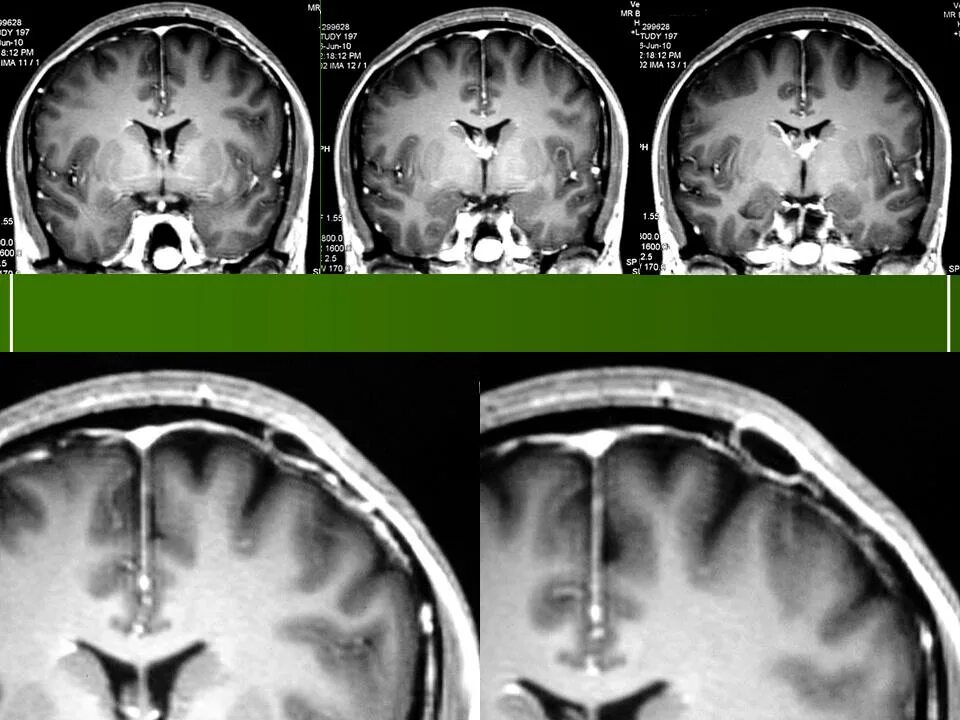

Ретроцеребеллярная ликворная киста